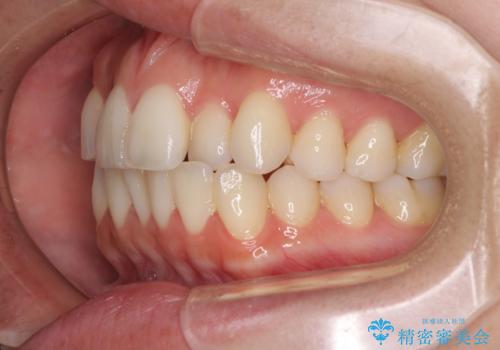

前歯のクロスバイト インビザラインによる矯正治療

- 上下のクロスバイトと前歯のデコボコを気にして来院された患者様です。

インビザラインを用い、IPR(歯と歯の間を削る)と歯列全体を拡大させることで、歯並びを整えていくこととしました。

治療を急いでいらっしゃらなかったため、のんびりと治療を進めていきました。3年以上の期間を要しましたが、きれいな口元に仕上がりました。